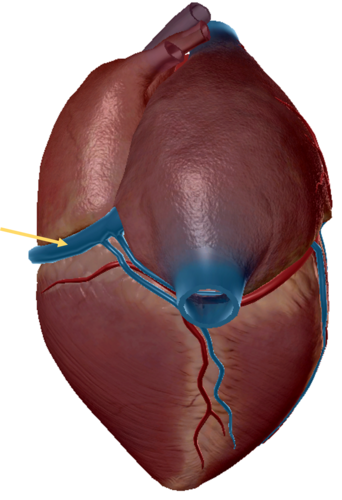

inferior vena cava

atrevoventricullar sulus

anterior inter ventricular sulcus

right coronary artery

great cardiac vein